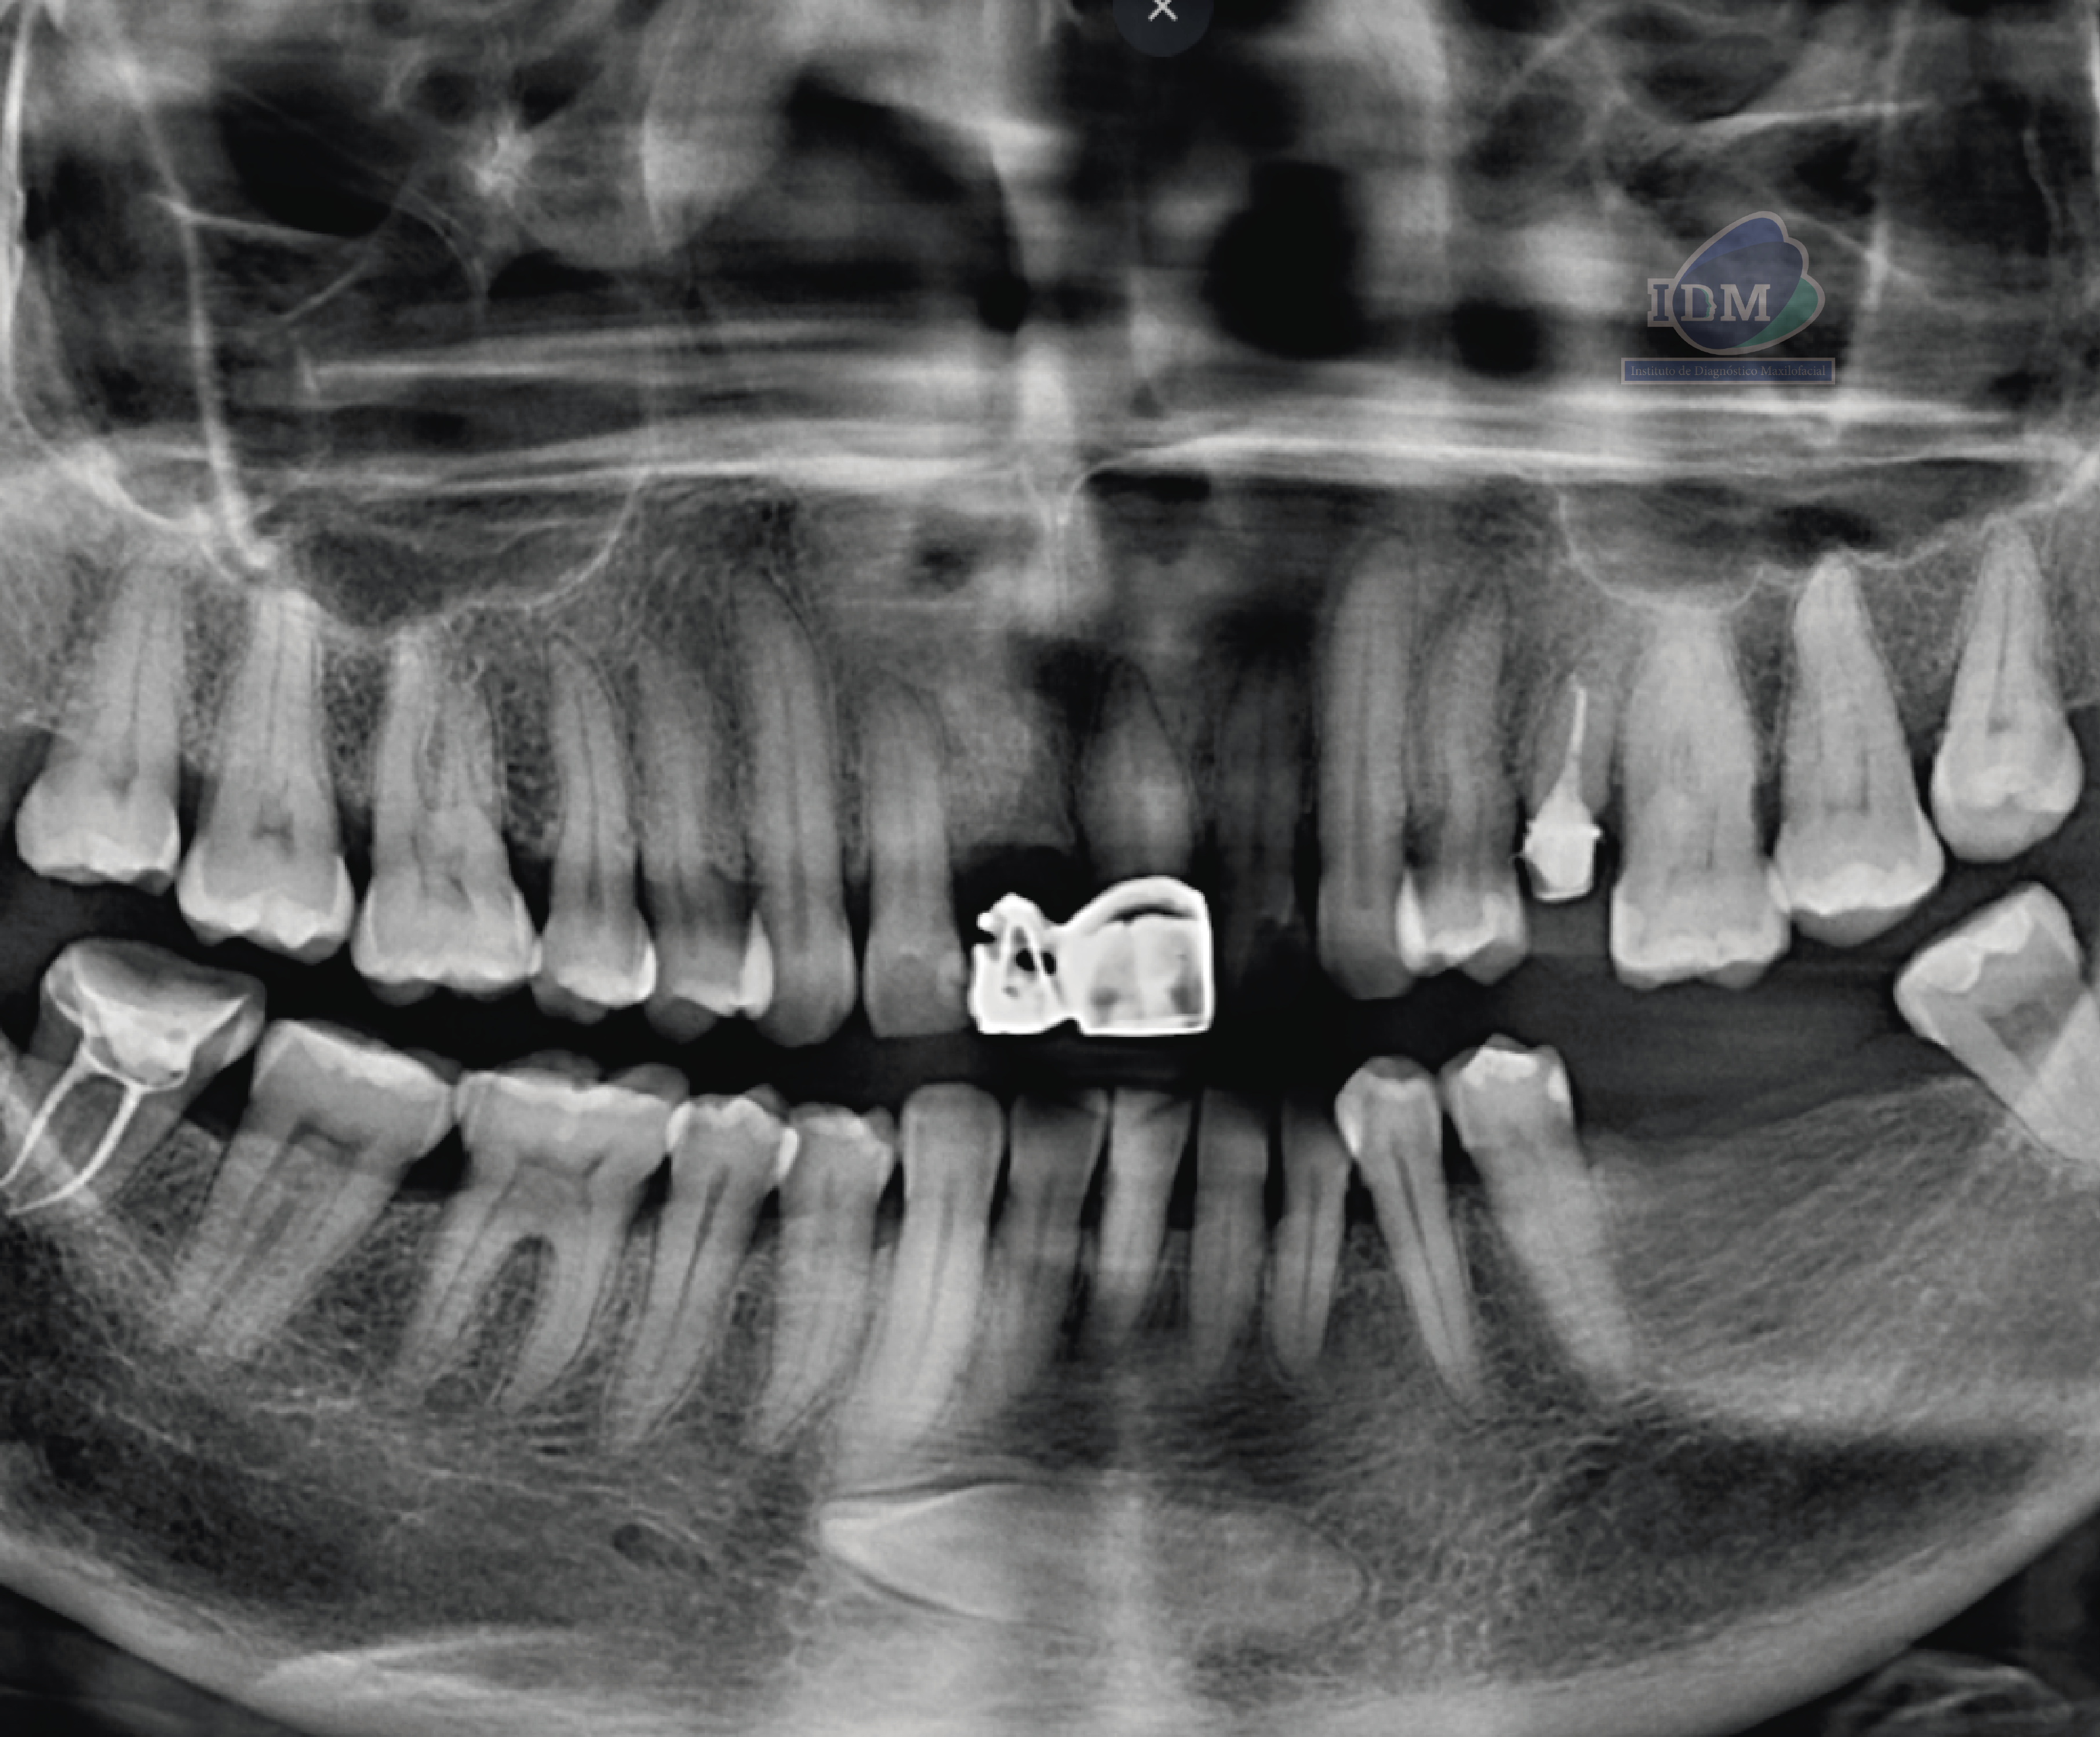

Radiografia Panorámica

A la evaluación de la radiografía panorámica se observa aplanamiento condilar bilateral, neumatización de ambos senos maxilares, presencia de placa mineralizada y reabsorción ósea del proceso alveolar, asimismo se observa múltiples restauraciones coronarias, las piezas 24 y 47 con tratamieto de conductos, pieza 21 con corona protésica, etc. Además, se observa la pieza 33 incluida en posición horizontal y proyectada a nivel de la sínfisis mandibular y con la porción coronaria orientada hacia el cuarto cuadrante a nivel apical de la pieza 43.